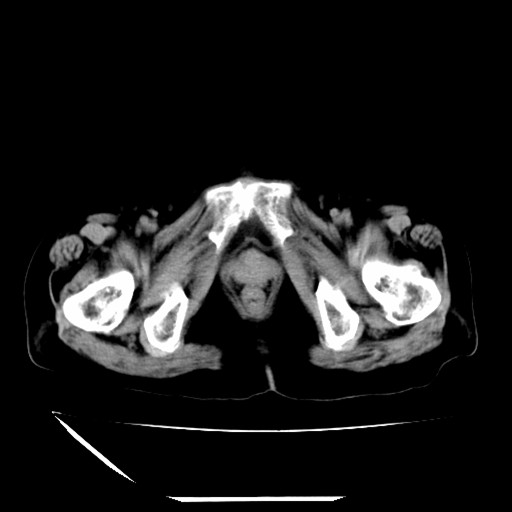

标题: CT16840:女-63岁,下腹部疼痛, [打印本页]

标题: CT16840:女-63岁,下腹部疼痛,

补充资料:血象是13.5,临床拟诊阑尾炎

本人诊断是右肾周围炎,阑尾炎,盆腔少许积液!

诊断右肾周围炎是因为我图像没有发完,诊断阑尾炎是因为相当于阑尾区连续两个层面可以看到增粗的阑尾显影。

支持阑尾炎!局部腹膜增厚,脂肪密度增高。应该手术治疗。